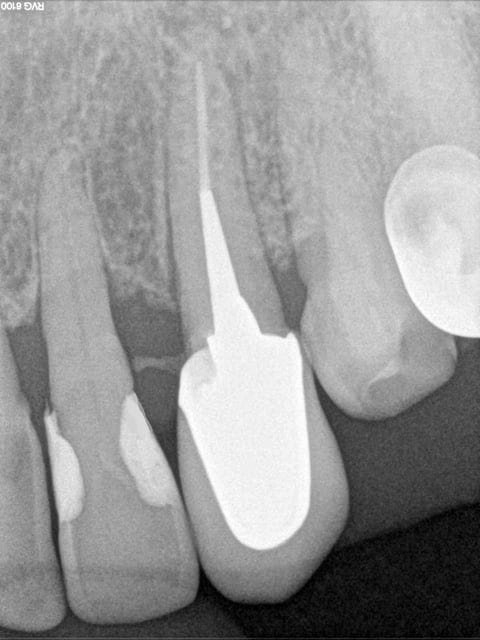

Il y a quelques temps un sujet avait mis le feu à la poudre d'oxyde de zinc .... Hodina s'était retrouvé avec une dent d'un patient dans la main et avait eu l'idée (saugrenue?)de la remettre...Il avait exprimé ses doutes dans le sujet : "1 ére fois que ça m'arrive" . S'en était suivi un débat passionné et passionnant où un certain Enlaye avait défrayé la chronique en exposant ses cas d'extractions / réimplantations ... (ERI !! ça le fait Enlaye) . Certains et même les plus nombreux avaient crié au fou !!! D'autres , dont moi , avaient prêté l'oreille , demandé des éclaircissements ... Bref , depuis Enlaye a gagné le respect des chantres de ce forum , il y apporte son humour , sa connaissance et son regard toujours intéressant ou drôle ,bref ,je suis fan ! (et ne chope pas la grosse tête , il y en a assez comme ça ici ! ) Cette idée d'extraction / réimplnatation me trottait dans la tête ...fallait que j'essaye : pas besoin de matos sophistiqué , pas besoin de formation ... fallait trouver le cas . Donc mi Novembre , une patiente de 71 ans se pointe avec une 23 cassée , sous gingival , à peine visible : la gencive ayant presque recouvert tout ça . Un stellite étant à dispo , je me dis : j'extrais et hop une adjonction .... Je prends une radio , la racine est belle .... Entre les 2 rendez vous , je cogite : et si ..... La fois suivante , je suis décidée , je vais tenter l'ERI , mon idée était de faire une "élongation coronaire" .... bref ..je vous passe les détails ... J'ai été enchantée du résultat !!! cela fait une semaine qu'elle a sa couronne définitive , sur une dent absolument pas mobile . Tout s'est super bien passé , aucune douleur (mis sous ATB) , certains diront que je suis allée un peu vite , mais bon , une provisoire c'est pas le top non plus . Alors , la conclusion de tout ça : j'y ai pris beaucoup de plaisir à tenter l'expérience , je ne dis pas que je recommencerais ça tous les jours ou même tous les mois. Je n'ai pas de recul sur cette dent , d'ici 6 mois , un an on verra ce que ça donne mais je ne pensais vraiment pas que cela soit possible alors je remercie Enlaye pour cette ouverture de mon petit esprit sclérosé , et je vous invite à tenter l'expérience .

Ha , ha , ha je savais que tu visais plus bas !! Bon je vais faire vite : alors endo in situ , sans digue ( waouh , mais t'es di(n)gue là ! remarque je me demande bien ou je l'aurais accroché le crampon , aux oreilles peut-être ?, alors plein de sales bébêtes sont passées par là , j'me demande même si j'étais pas enrhumée ce jour là .. ça c'est pour Ameli !!! ) . La fois suivante , je réalise une provisoire mais le hic c'est que le logement de tenon ,ben j'arrivais pas à avoir une longueur satisfaisante , ça butait sur les dents adjacentes .... Prov en tab 2000 et moule ... Puis vient le grand jour de l'extraction réimplantation : je vire manteau , sac , chaussures ..... hi hi hi .. bon rien en fait ! Je m'arme d'un bon petit davier et la dent, sympa comme la patiente, vient facilement ! Et là tout devient plus facile , je refais mon logement de tenon à la bonne longueur (trop facile!) et j'ajuste ma provisoire aux petits oignons ... surtout en distal et mésial bien sûr . Et je remets gentiment tout ça en place . Pb , ça ballote dans tous les sens ! ouille ouille , mal barré mon affaire ! J'avais prévu une contention avec une grille et du compo fluide : pb le compo sur de la résine ça tient pas bien ! et la dent se balade quand même un peu . je m'y reprends à 2 ou trois fois avant que j'obtienne un truc qui tienne.Bon faut pas y aller franco non plus . Ce qui m'a aidé ( et a aussi facilité ma décision) c'est qu'en antagoniste , il y avait une PAP .. donc une certaine souplesse !!!Le hic , c'est que pour l'élongation coronaire ben c'est pas ça , la coquine est retournée bien sagement dans son cocon . Bon bon bon , on verra . La patiente est cool , et prévenue qu'il va pas falloir croquer des smarties de ce coté là , je la mets sous ATB et roule ma poule ! J'attends la semaine suivante avec curiosité mais une pointe d’anxiété quand même : a t-elle expulsé sa valda en éternuant ? s'est elle tordue de douleur ? la contention a t'elle tenu ? Et la semaine suivante : tout va bien : pas de douleur , la dent et sa provisoire sont là . Tuti va bene ! Rendez-vous 5 semaines plus tard : faut que j'en ai le cœur net : je dépose ma contention qui ne résiste vraiment pas beaucoup ! je teste la mobilité : nada , rien ! tout va bien . La gencive est impeccable,un miracle ! le jonction gencive , dent est bien nette : que demande le peuple ! La suite est classique . Voili , voilà ;

Par contre t'as du reste de ciment il me semble !

Oui entre 22 et 23, non ?

Il est certain que ce n'est pas donné à tout le monde ! si tu zieutes les radio à la loupe , si t'es un adepte compulsif de cone beam à la recherche de chaque imperfection de la cavité buccale (on parle pas du reste du corps , hein ! ) ben c'est pas pour toi . Le ciment ? apparemment ça vous inquiète , il va partir bien gentiment , j'ai bien vu ce petit truc à la radio , j'ai cherché j'ai rien trouvé : des papilles en béton : ça doit être ça !